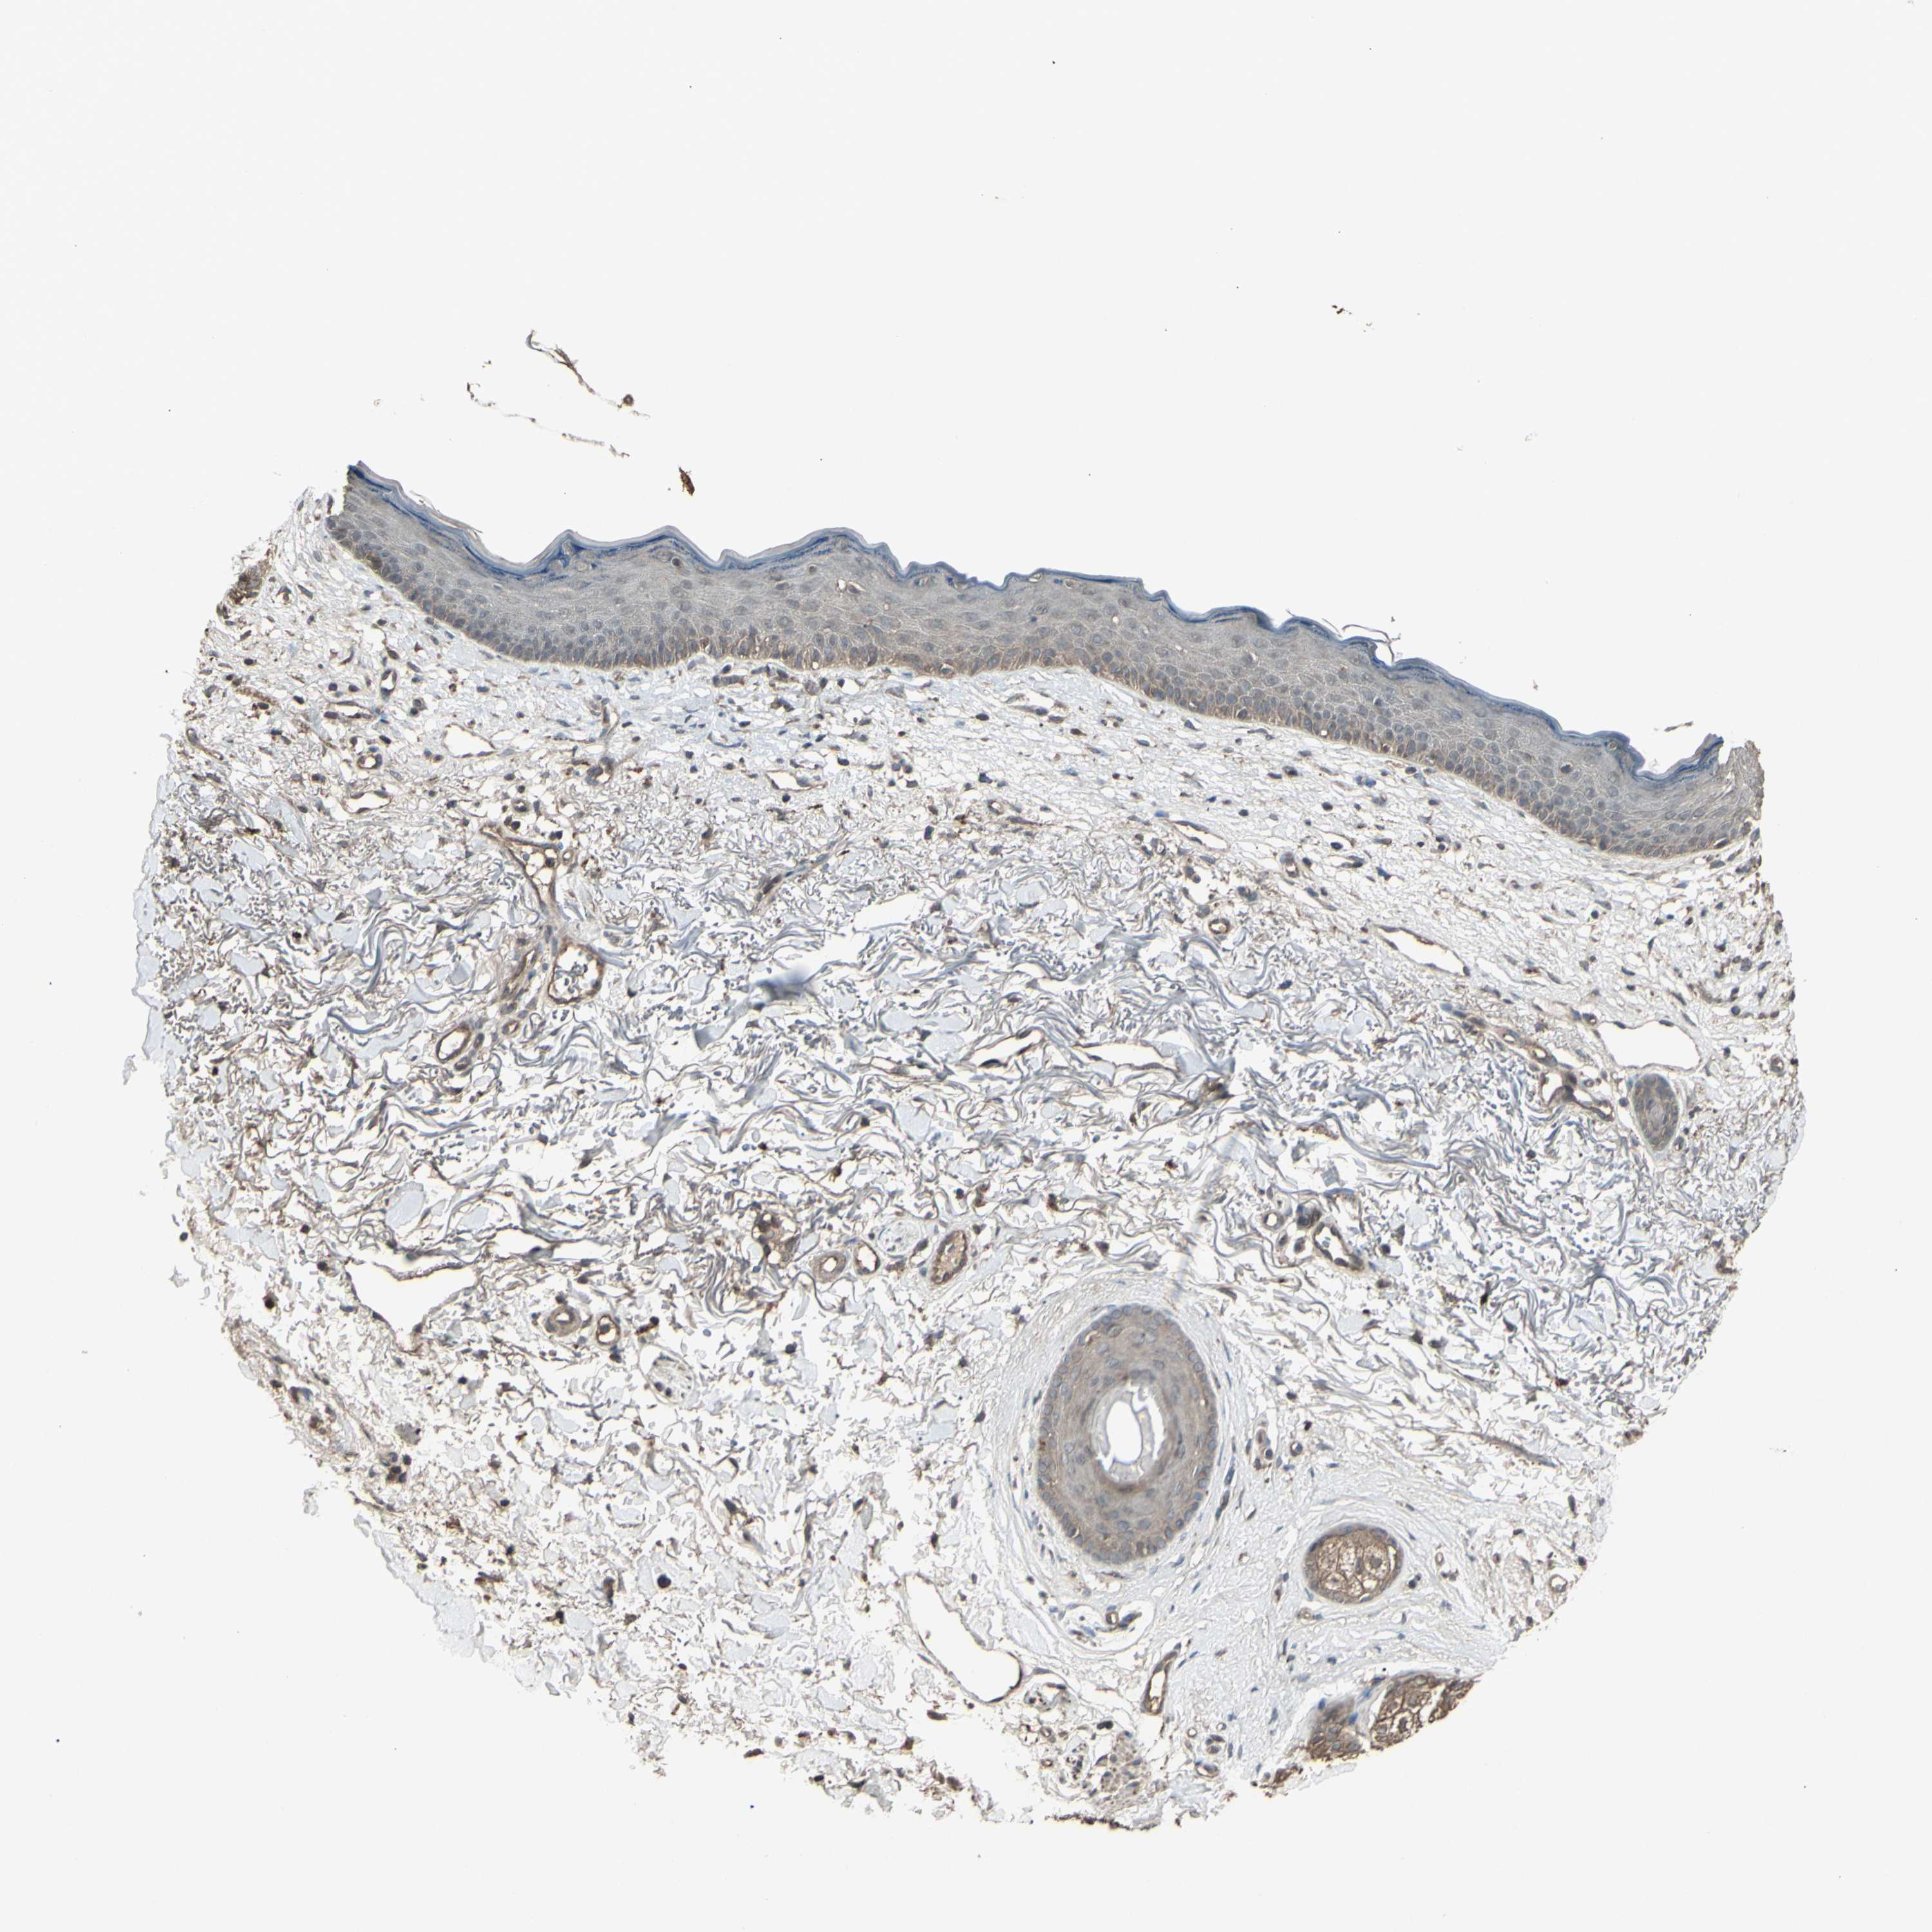

SKIN CANCER - Protein expressioni

A mouse-over function shows sample information and annotation data. Click on an image to view it in a full screen mode. Samples can be filtered based on level of antibody staining by selecting one or several of the following categories: high, medium, low and not detected. The assay and annotation is described here.

Each image is clickable and will lead to virtual microscopy that enables deeper exploration of all samples and also displays staining intensity scores, fraction scores and subcellular localization as well as patient and tissue information for each sample.

Antibody HPA027478

Squamous cell carcinoma, NOS